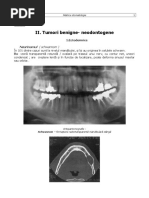

Diagnosticul: radiografia panoramică indică direcţia şi liniile de fractură, raportul cu fosele

nazale, sinusul maxilar, tuberozitatea, apo- fizele pterigoidiene, raportul cu apexurile dinţilor,

gradul de dislocare a fragmentelor. Diagnosticul diferenţiat se efectuează în fractura apofizei

alveolare, fracturi Le Fort, fracturi mediosagitale.

Diagnosticul – radiografia panoramica indica directia si liniile de fractura, raportul cu fosele

nazale, sinusul maxilar, tuberozitatea, apofizele pterigoidiene, raportul cu apexurile dintilor,

gradul de dislocare a fragmentelor.